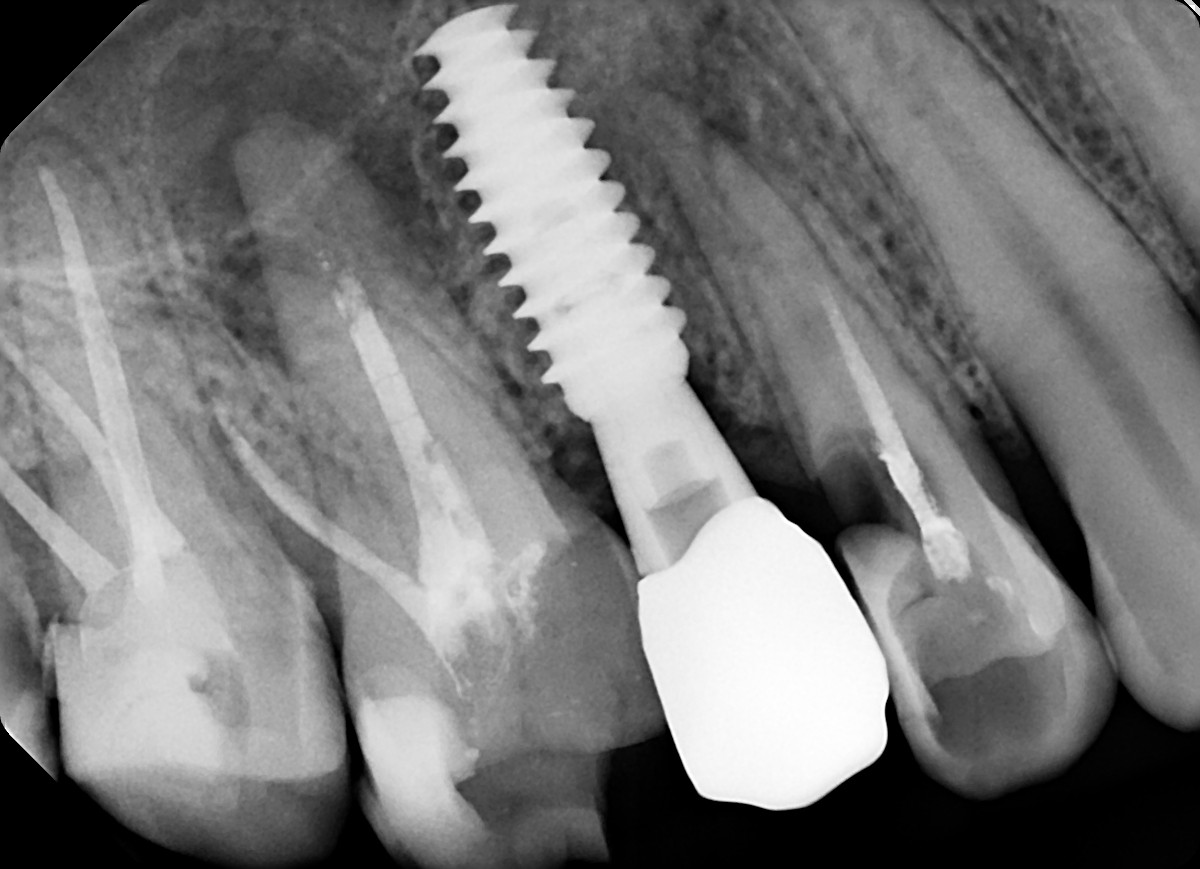

10. What option can explain the restoration on the implant?